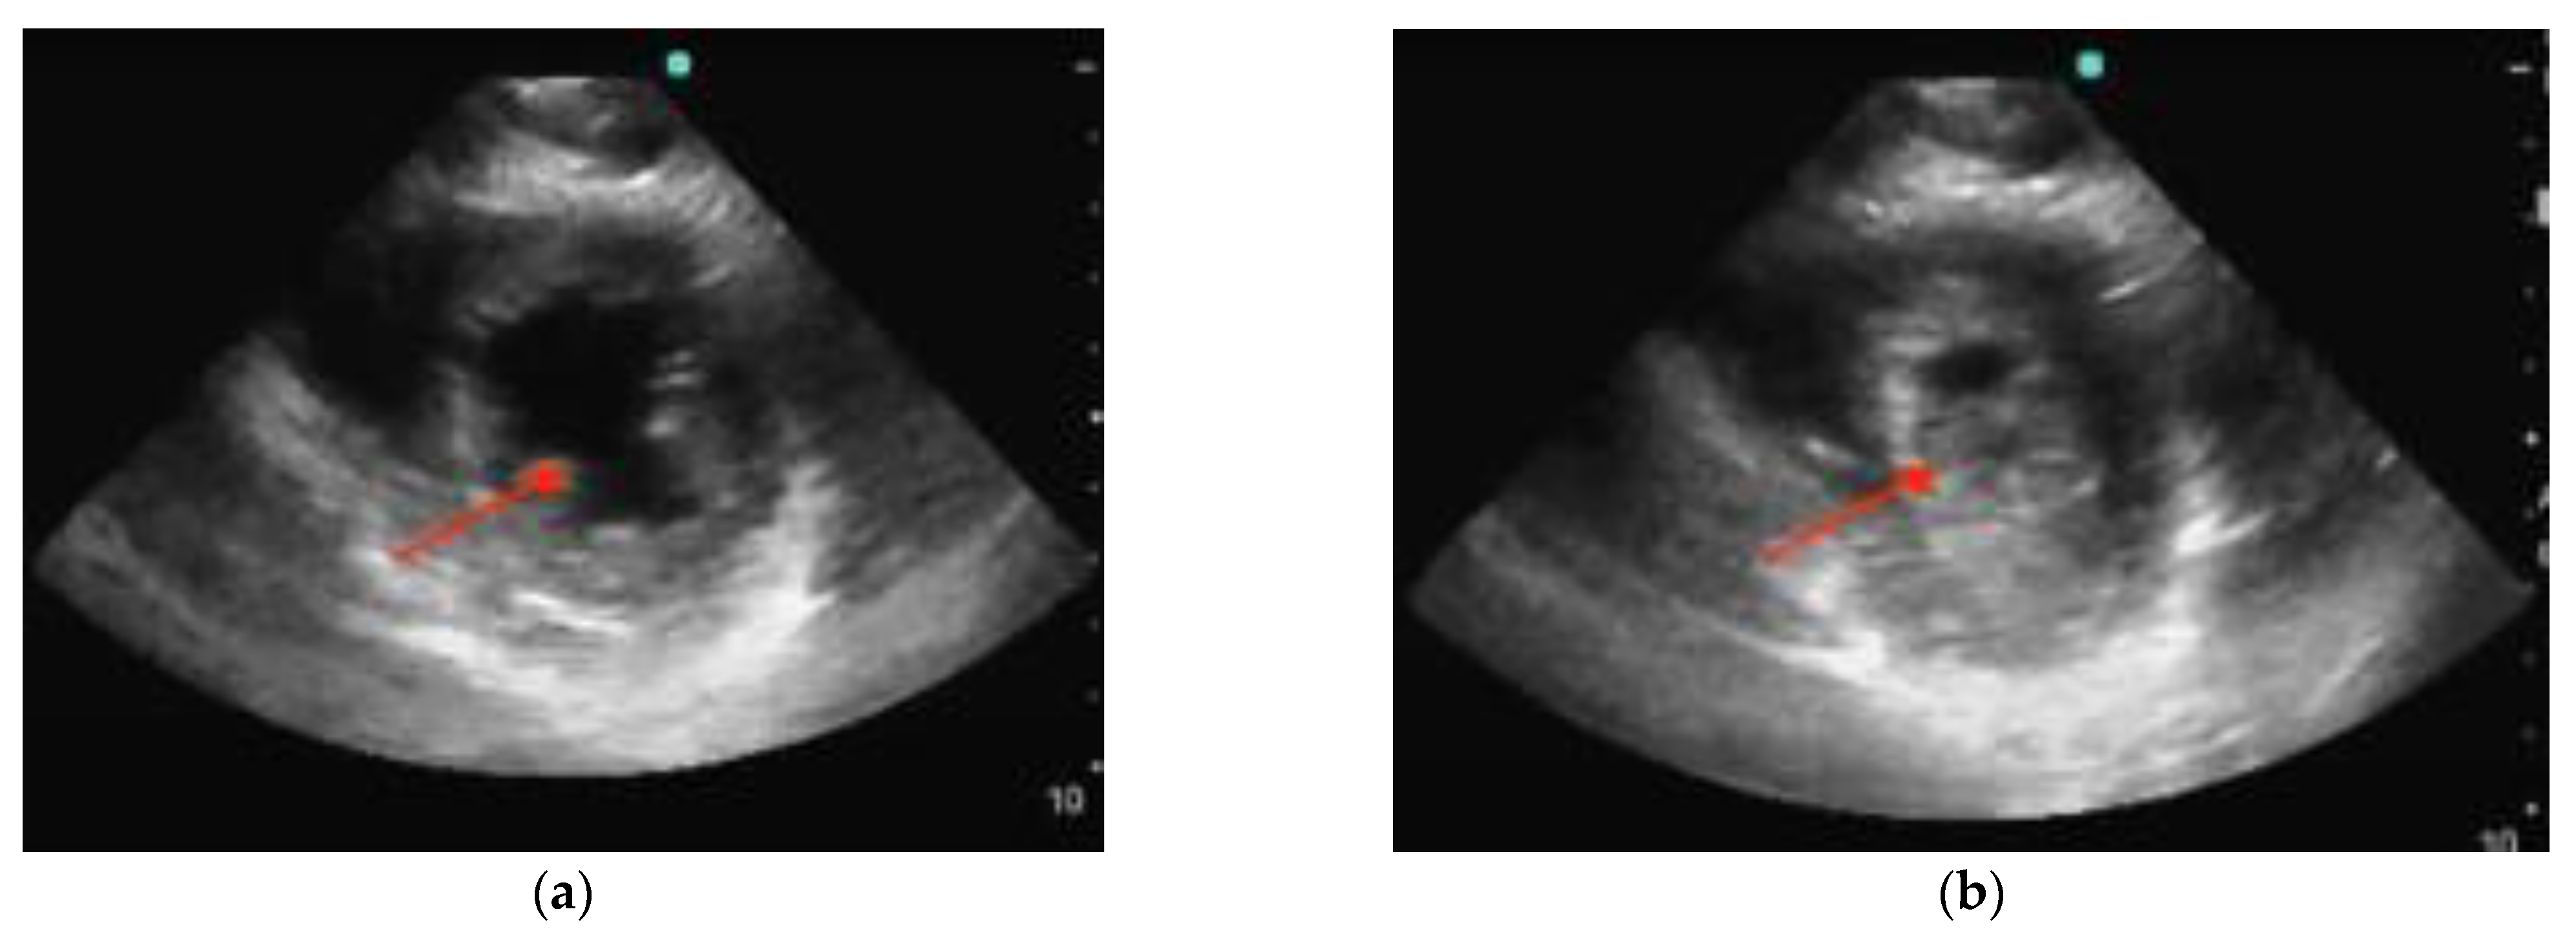

POCUS can be focused on a cardiac view or it can include other windows. In performing POCUS during cardiac arrest, the ideal probe is dependent on the goal. A phased array transducer, working at low frequencies (1–5 Hz) and providing high resolution, is usually adopted as the cardiac probe. A linear transducer (7–15 MHz) is optimal for the lung window and pneumothorax, thereby allowing via its high frequencies detailed imaging of the pleural line [7,8]. Deep tissue and abdomen evaluation is best carried out with a convex probe characterized by a wide footprint and frequencies ranging from 2.5 to 7.5 MHz. Regardless of the availability of different probe options, it is preferable to mostly rely on one probe, preferably a phased-array probe, during cardiac arrest scenarios. This is because the phased-array probe offers versatility and comprehensive assessment capabilities, thus allowing for efficient evaluation of both cardiac activity and lung function. The main difference between echography during cardiac arrest and standard echography lies in the approach and timing used. Rapid acquirement of a single view is the aim during the critical event of cardiac arrest where precious seconds cannot be spent evaluating multiple measurements and views as is the case with standard echography. With this objective in mind, the subxiphoid approach has traditionally been the preferred window as it can be performed during ongoing CPR. Nonetheless, the parasternal long-axis view demonstrated superiority compared to the subxiphoid view regarding the rapidity of execution as well as the quality of the cardiac image [9] (Figure 1). Ultimately, patient characteristics (e.g., body habitus), as well as the environment and the accessibility to the patient (particularly in a prehospital context), may dictate the best view for each situation [9,10].

Figure 1.

Normal parasternal long-axis view (a) and subxiphoid view (b). RV = right ventricle, LV = left ventricle, MV = mitral valve, DA = descending aorta, AA = ascending aorta, and AV = aortic valve.